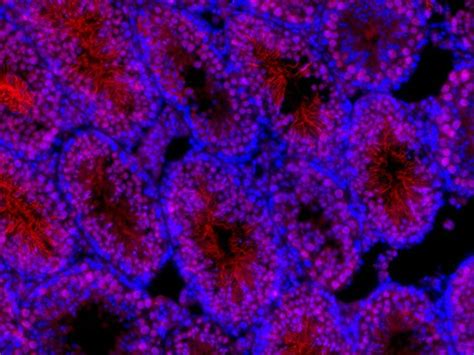

PRM1 antibody (15697-1-AP) | Proteintech

PRM1 Antibody

PRM1 Prm2

Flowchart of PRM1 and Prm2 in Spermatogenesis